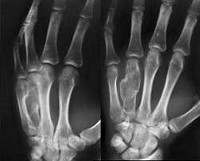

Это редко встречающееся новообразование, содержащее кисты, заполненные кальцинатом. Неоплазия локализуется преимущественно в трубчатых костях, поражая дистальные и проксимальные отделы. Опухоль возникает из незрелых клеток хрящевой ткани, формируясь в бедренной, большеберцовой, таранной, тазовой, плечевой кости, в области стопы и лопатки. Хондробластома представляет собой нарост грязно серого или бурого цвета, с очагами обызвествления, кровоизлияния, аневризматическими кистами. Вокруг очага наблюдается отечность. Опухоль медленно прогрессирует, постепенно разрушая суставы и кость, что делает ее небезопасной, тем более имеется тенденция к ее перерождению в злокачественную форму. Достоверно неизвестно, что влияет на появление хондробластомы, также спорный вопрос вызывает ее происхождение.